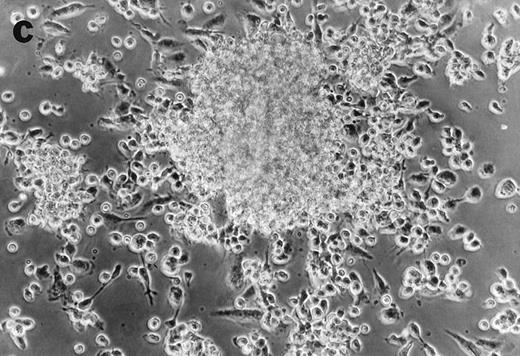

CD34+cells treated with GTS yielded numerous typical DC colonies in methylcellulose after ≈12 days, as expected (Fig 4a).19 GTS cultures treated with anti-TNF also yielded numerous CFUs. However, most of the colonies consisted of small round cells (Fig 4b) and few, if any, typical DC colonies were observed. In comparison to liquid GTS cultures which contained many adherent DC clusters (Fig 4c), the liquid anti-TNF–treated GTS cultures contained predominantly nonadherent cells around day 10 (Fig 4d). Examination of these nonadherent cells under higher magnification showed that they were either small round cells or veiled cells.

Anti-TNF–treated GTS cultures produce distinct progeny in methylcellulose and liquid cultures, compared with GTS cultures. GTS cultures yielded typical DC colonies around day 12 in methylcellulose (a) and adherent DC clusters in liquid cultures (c). In methylcellulose, anti-TNF–treated GTS cultures produced large CFUs containing small round cells and lacking typical DCs (b). The liquid anti-TNF–treated cultures (d) contained predominantly nonadherent cells. Original magnification × 20.